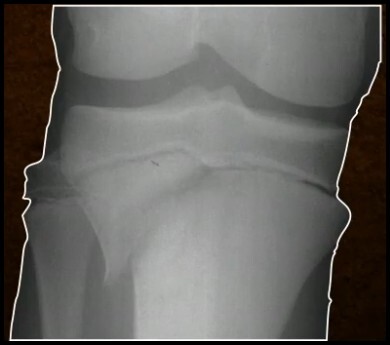

16

Q

FX Tíbia Proximal

FX Metafisária - TTO (2)

A

• TTO Conservador → Redução Fechada + Gesso Inguinopodálico

• TTO CX → Grandes desvios / interposição pata de ganso

Complicação → Valgo Progressivo

17

FX Metafisária - Valgo progressivo

1. Inicio 6 meses após a FX

2. Progride com 2 anos de evolução

3. Melhora em 3 - 4 anos